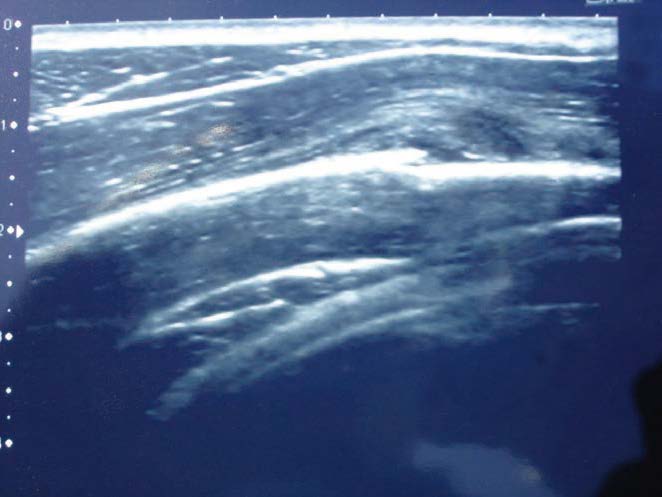

Echographie d’une fracture de fatigue de côte.

Les fractures de fatigue costales apparaissent dans des mouvements stéréotypés qui imposent au levier costal des contraintes itératives en flexion, en compression et en torsion, à l’origine d’une douleur pariétale localisée.

L’objectif de l’imagerie est de préciser le diagnostic et d’éliminer des pathologies osseuses d’origine non sportive telles qu’une tumeur ou une infection. Cependant, il est à noter que, quelle que soit la localisation de la fracture, la radiographie n’est positive que dans 15 % des cas en phase précoce et qu’elle resterait négative dans 50 % des cas en phase tardive. Si une image est visible, il existe une certitude diagnostique mais celle-ci peut n’apparaître qu’après un délai de 2 à 3 semaines, à la période où la consolidation commence à se faire.